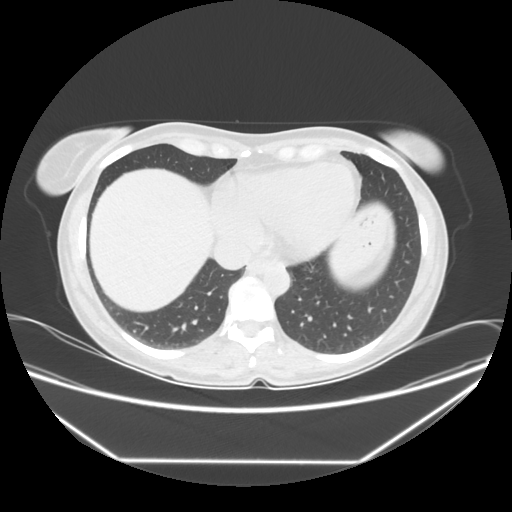

Image Grid

4Γ—3 grid: Rows show different image types (Original NATIVE, Reconstructed NATIVE, Original VENOUS, Generated VENOUS), Columns show windowing techniques (No Window, Lung Window, Mediastinum Window)

Reconstructed NATIVE CT scan (cycle consistency)

Lung window (WL -600, WW 1500 β†’ Low βˆ’1350, High +150)

Mediastinum window (WL 40, WW 400 β†’ Low βˆ’160, High +240)

Generated VENOUS CT scan (A→B translation)